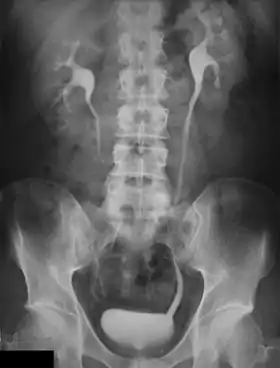

An Example of an IVU radiograph

An intravenous pyelogram (IVP), also called an intravenous urogram (IVU), is a radiological procedure used to visualize abnormalities of the urinary system, including the kidneys, ureters, and bladder. Unlike a kidneys, ureters, and bladder x-ray (KUB), which is a plain (that is, noncontrast) radiograph, an IVP uses contrast to highlight the urinary tract.